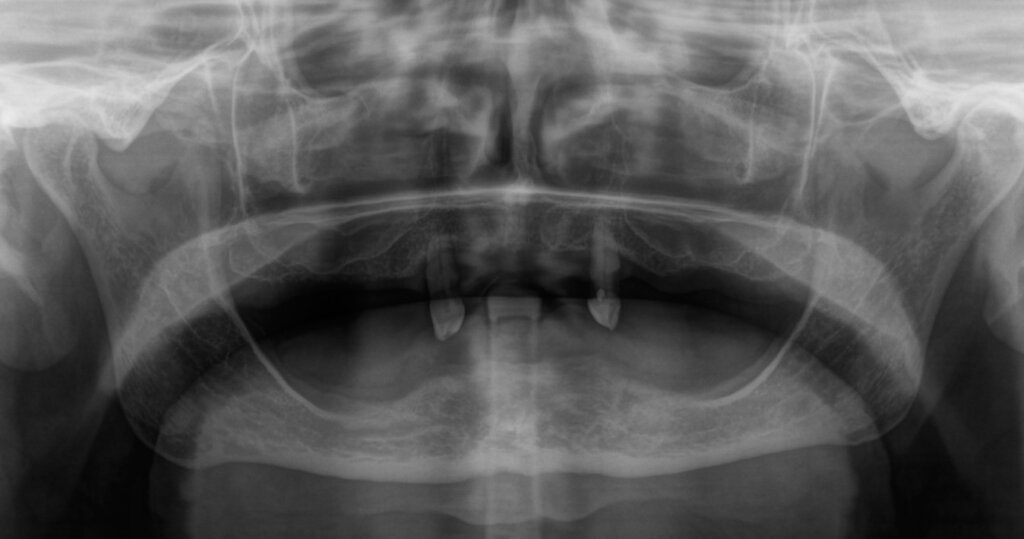

Before Zygomatic Implant Procedure

After Zygomatic Implant Procedure